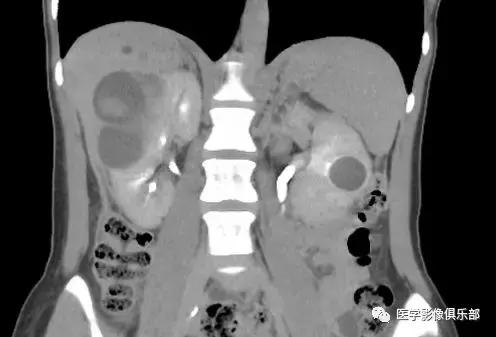

[典型病例二]:45岁,女性患者,腹部不适。家族史是动脉瘤性蛛网膜下腔出血和肾损害。

CTMPR冠状位重建显示双侧肾脏体积明显增大,肾脏皮质及髓质分界不清,弥漫大小不等的囊肿,边界光滑锐利,肝脏实质内亦可见多发大小不等的囊肿。